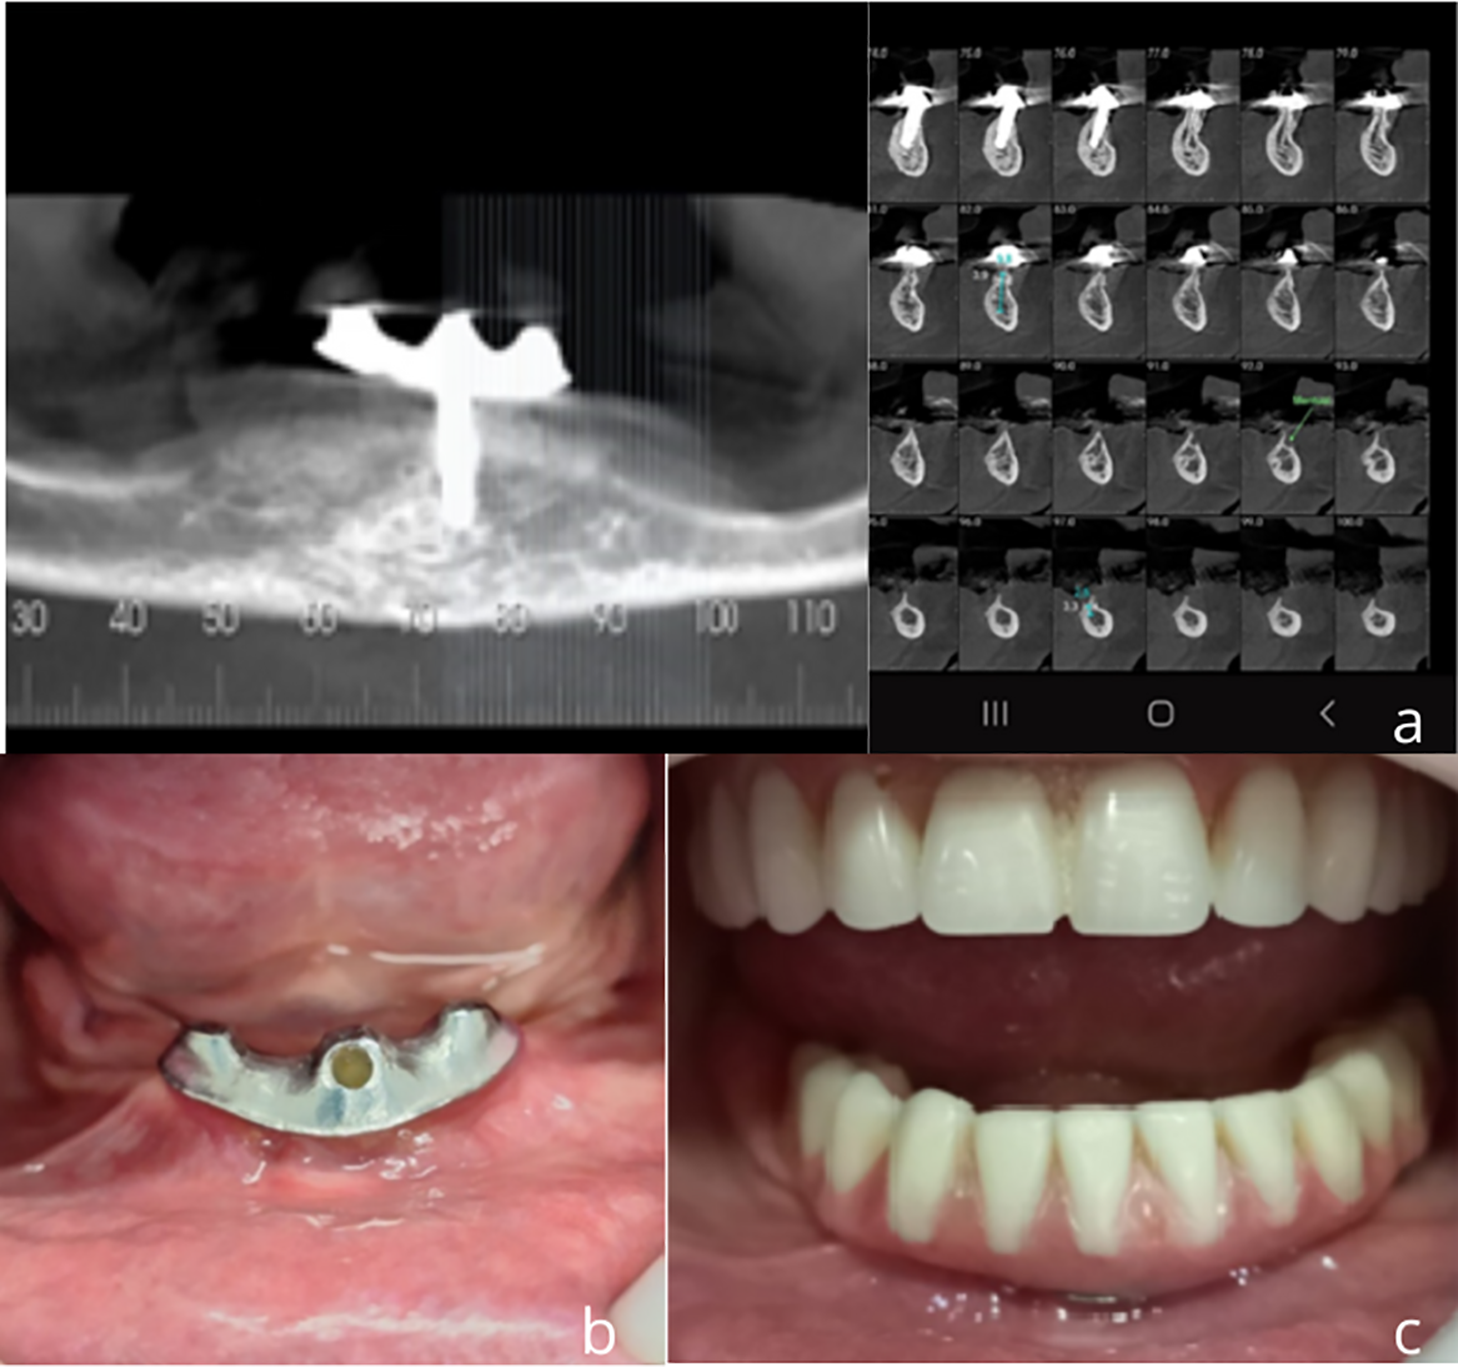

Fig. 3. Five-year follow-up (2024)–a) CBCT image at 5 years; b) clinical view of the T-OVER abutment and c) the complete mandibular overdenture.

Fig. 2 illustrates the baseline clinical conditions (2019), including the initial CBCT, implant placement, T-OVER fabrication, and intraoral clinical and radiographic images of the installed abutment and prostheses. Fig. 3 presents the 5-year follow-up (T2, 2024), including updated CBCT images, clinical view of the T-OVER abutment, and prosthesis in function. The most common intervention was pressure adjustment to achieve adequate retention (N = 3).